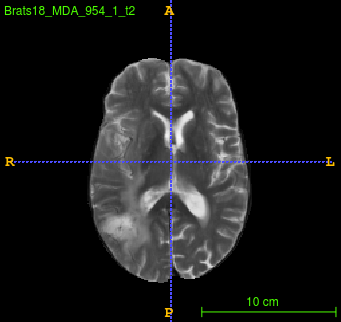

Segmentation of brain tumor from magnetic resonance imaging (MRI) is a vital process to improve diagnosis, treatment planning and to study the difference between subjects with tumor and healthy subjects. In this paper, we exploit a convolutional neural network (CNN) with hypercolumn technique to segment tumor from healthy brain tissue. Hypercolumn is the concatenation of a set of vectors which form by extracting convolutional features from multiple layers. Proposed model integrates batch normalization (BN) approach with hypercolumn. BN layers help to alleviate the internal covariate shift during stochastic gradient descent (SGD) training by zero-mean and unit variance of each mini-batch. Survival Prediction is done by first extracting features(Geometric, Fractal, and Histogram) from the segmented brain tumor data. Then, the number of days of overall survival is predicted by implementing regression on the extracted features using an artificial neural network (ANN). Our model achieves a mean dice score of 89.78%, 82.53% and 76.54% for the whole tumor, tumor core and enhancing tumor respectively in segmentation task and 67.90% in overall survival prediction task with the validation set of BraTS 2018 challenge. It obtains a mean dice accuracy of 87.315%, 77.04% and 70.22% for the whole tumor, tumor core and enhancing tumor respectively in the segmentation task and a 46.80% in overall survival prediction task in the BraTS 2018 test data set.